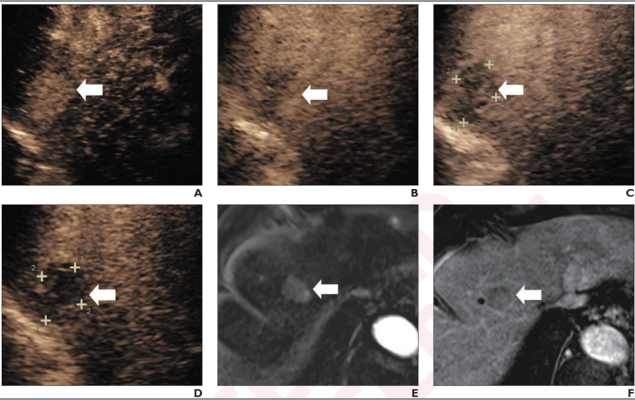

71-year-old woman at high-risk for HCC due to chronic hepatitis B. Patient underwent CEUS using perfluorobutane. (A) Arterial-phase CEUS image (12 seconds after injection) shows 25-mm segment-8 lesion with nonrim hyperenhancement (arrow). (B) CEUS image in portal-venous phase (48 seconds) shows corresponding early washout (arrow). (C) CEUS image in late phase (2 minutes) shows corresponding late and mild washout (arrow). (D) CEUS image in Kupffer phase (15 minutes) shows marked Kupffer defect (arrow). Patient also underwent evaluation by dynamic contrast-enhanced MRI using gadoxetate disodium. (E) Axial arterial-phase image shows 23-mm segment-8 lesion with nonrim arterial phase hyperenhancement (arrow). (F) Axial portal-venous phase image shows corresponding nonperipheral washout (arrow). Observation was classified as LR-M by modified CEUS criteria using perfluorobutane, and as LR-5 by CT/MRI LI-RADS v2018. Pathologic diagnosis based on surgical resection was intrahepatic cholangiocarcinoma.

November 17, 2022 — According to an accepted manuscript published in ARRS’ American Journal of Roentgenology (AJR), diagnostic performance of LR-5 for hepatocellular carcinoma (HCC) diagnosis was not significantly different between modified contrast-enhanced ultrasound (CEUS) using perfluorobutane and CT/MRI LI-RADS version 2018.

“The findings support the application of modified CEUS criteria using perfluorobutane for diagnosing HCC in high-risk patients,” wrote Jianhua Zhou, MD, PhD, of Sun Yat-Sen University Cancer Center’s State Key Laboratory of Oncology in Guangzhou, South China.

In this AJR accepted manuscript, 171 patients (140 men, 31 women; mean age, 54 years) at high risk for HCC with a pathologically confirmed liver observation were evaluated by both CEUS using perfluorobutane and contrast-enhanced CT or MRI, between March 2020 and May 2021. A matching algorithm was used to select 2 patients with HCC for each patient with a non-HCC lesion. Two readers evaluated observations using proposed modifications to CEUS LI-RADS version 2017 that classify certain observations as LR-5—rather than LR-4 or LR-M, based on presence of defect post-perfluorobutane administration.

Ultimately, modified CEUS criteria using perfluorobutane and CT/MRI LI-RADS v2018 showed no significant difference in sensitivity (92.1% vs. 89.5%), specificity (87.9% vs. 84.2%), or accuracy (90.6% vs. 87.7%) of LR-5 for HCC. All observations assigned LR-4 (n=5) or LR-M (n=6) by CT/MRI LI-RADS v2018 but LR-5 by modified CEUS were HCC.

“Modified CEUS criteria performed similarly as CT/MRI LI-RADS v2018 and additional HCCs in a subset of observations assigned LR-4 or LR-M by CT/MRI LIRADS v2018,” the authors of this AJR accepted manuscript reiterated.